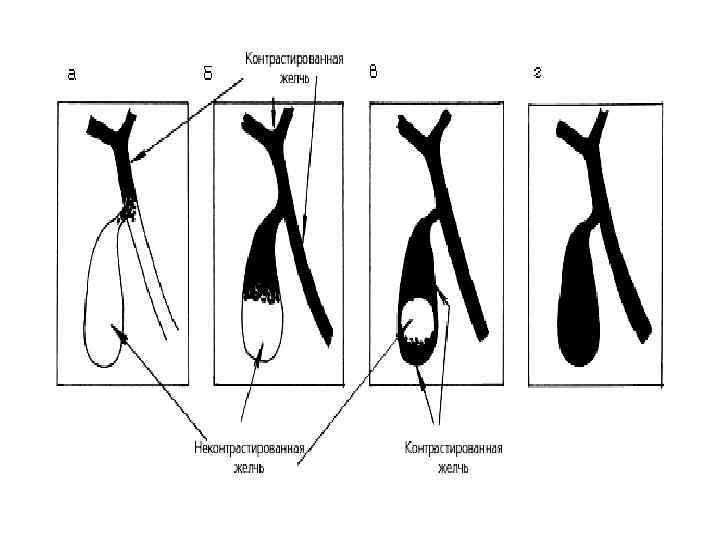

Холекинез • Заполнение жёлчного пузыря

Холекинез • Заполнение жёлчного пузыря

Холекинез: выделение жёлчи в кишечник Порции жёлчи

Холекинез: выделение жёлчи в кишечник Порции жёлчи